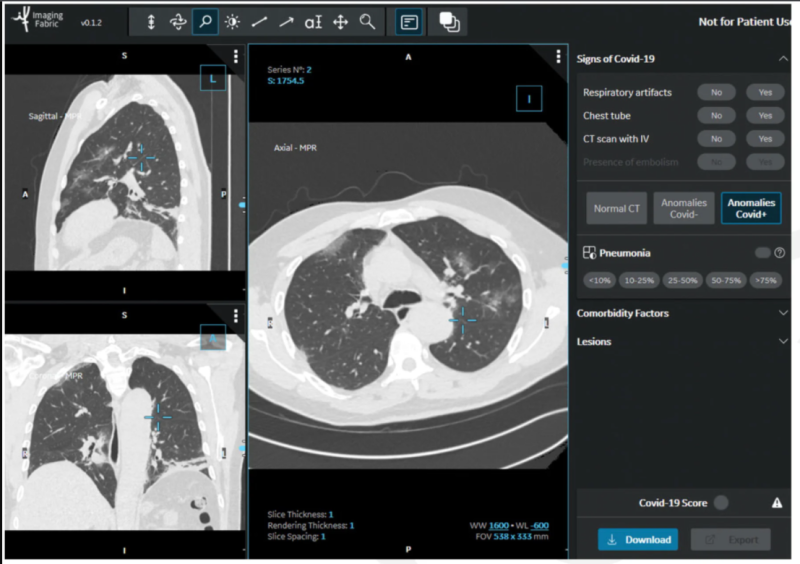

This photo gallery shows the variety of radiological presentations of COVID-19 (SARS-CoV-2) in medical imaging, including computed tomography (CT), radiograph X-rays, ultrasound, echocardiograms and magnetic resonance imaging (MRI). The radiology images show examples of typical COVID pneumonia in the lungs and the numerous complications the virus causes in the body in multiple organs, including the brain, kidneys, heart, abdomen and vascular system.

Ultrasound, especially hand-held ultrasound imaging devices, have become a primary imaging modality for novel coronavirus because of the ease to bag the device and sterilize it after use. CT and mobile X-ray systems are also used as front-line imaging systems for COVID-positive or suspected COVID patients.